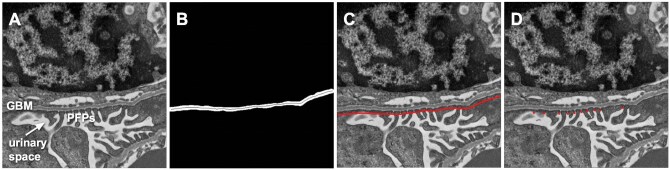

Transmission electron microscopy (TEM) images can visualize kidney glomerular filtration barrier ultrastructure, including the glomerular basement membrane (GBM) and podocyte foot processes (PFP). Podocytopathy is associated with glomerular filtration barrier morphological changes observed experimentally and clinically by measuring GBM or PFP width. However, these measurements are currently performed manually. This limits research on podocytopathy disease mechanisms and therapeutics due to labor intensiveness and inter-operator variability. We developed a deep learning-based digital pathology computational method to measure GBM and PFP width in TEM images from the kidneys of Integrin-Linked Kinase (ILK) podocyte-specific conditional knockout (cKO) mouse, an animal model of podocytopathy, compared to wild-type (WT) control mouse. We obtained TEM images from WT and ILK cKO littermate mice at 4 weeks old. Our automated method was composed of two stages: a U-Net model for GBM segmentation, followed by an image processing algorithm for GBM and PFP width measurement. We evaluated its performance with a 4-fold cross-validation study on WT and ILK cKO mouse kidney pairs. Mean [95% confidence interval (CI)] GBM segmentation accuracy, calculated as Jaccard index, was 0.73 (0.70-0.76) for WT and 0.85 (0.83-0.87) for ILK cKO TEM images. Automated and manual GBM width measurements were similar for both WT (P = .49) and ILK cKO (P = .06) specimens. While automated and manual PFP width measurements were similar for WT (P = .89), they differed for ILK cKO (P < .05) specimens. WT and ILK cKO specimens were morphologically distinguishable by manual GBM (P < .05) and PFP (P < .05) width measurements. This phenotypic difference was reflected in the automated GBM (P < .05) more than PFP (P = .06) widths. Our deep learning-based digital pathology tool automated measurements in a mouse model of podocytopathy. This proposed method provides high-throughput, objective morphological analysis and could facilitate podocytopathy research.